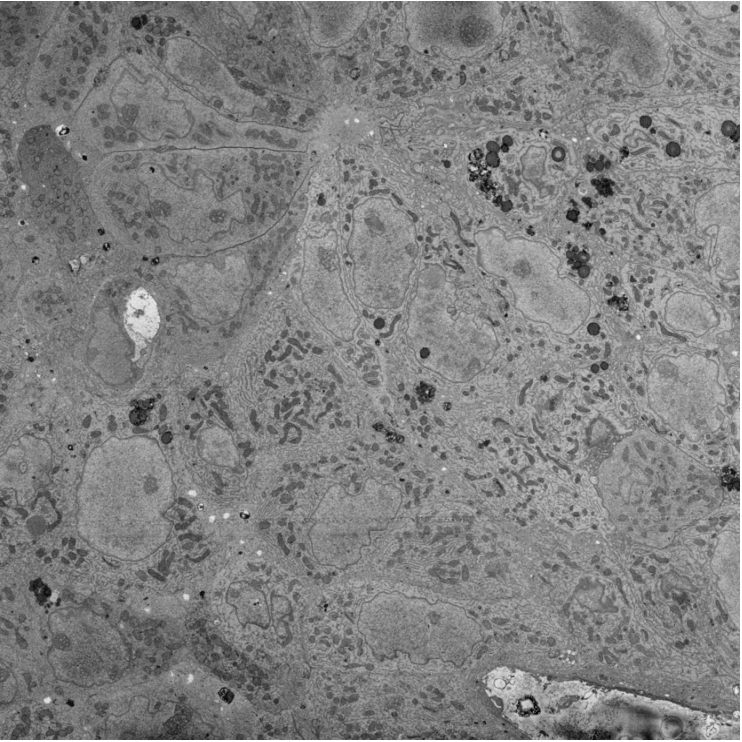

SEM image

Refer to caption

(a)

Ground truth cell contour

(b)

Simulated probability map

(c)

Zoom into a local isotropic diffusion area

(d)

Zoom into a local dropout area

(e)

Figure 3: Typical data used for the end-to-end supervised training of the cell contour closing network. (a): private tumour SEM image, (b): corresponding ground truth cell contour , (c): simulated cell contour probability map derived from (b) using Eq. (1), (d): zoom into the red square in (c) highlighting a global and local isotropic diffusion of cell contour probability, (e): zoom into the purple square in (c) highlighting a local lack of cell contour probability.